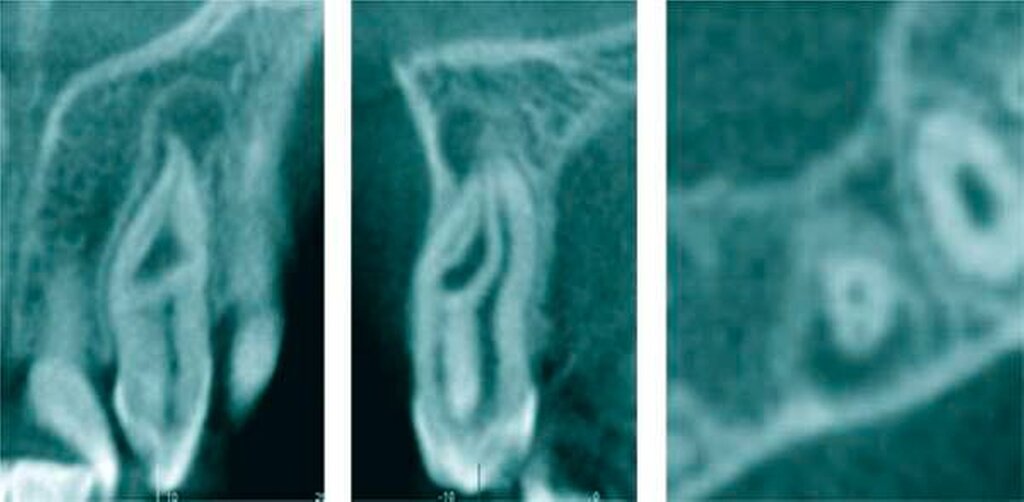

Zapfenförmige seitliche Schneidezähne können ein Hinweis auf eine abweichende Form des Wurzelkanalsystems sein. So können mehrfach gekrümmte Wurzelkanäle beobachtet werden. Darüber hinaus können auch Fehlentwicklungen des äußeren Schmelzepithels auftreten und als Ursache für scheinbar untypische pulpitische Beschwerden bei fehlender Karies verantwortlich sein (Abbildung 13). Invaginationen des äußeren Schmelzepithels können in unterschiedlich tiefer Ausprägung auftreten [Tomas, 1974]. Die Prävalenz dentaler Invaginationen liegt zwischen 3 und 10 Prozent, wobei sie in bis zu 70 Prozent der Fälle bilateral auftreten [Thomas, 1974; Gotoh, 1979; Hülsmann, 1995]. Nach Oehlers werden drei Grade unterschieden [Oehlers, 1957]. Insbesondere Typ-II-Invaginationen mit einer Einstülpung bis unterhalb der Schmelz-Zement-Grenze können bei mikrobieller Infektion aufgrund der Nähe zur Pulpakammer eine irreversible Pulpitis und eine nachfolgende Pulpanekrose auslösen. Im Fall eines Dens invaginatus vom Typ III besteht zwischen der Eintrittspforte an der klinischen Zahnkrone und dem apikalen Endpunkt ein vom Wurzelkanal unabhängiger Verlauf [Hülsmann, 1995]. Die Infektion eines Dens invaginatus kann deshalb röntgenologisch zu einer periapikalen Aufhellung bei fortbestehender Sensibilität des Zahnes führen (Abbildung 14). Eine minimalinvasive Invaginationstherapie kann den Erhalt der Pulpa ermöglichen (Abbildung15).

Bei einem ausgeprägten Foramen caecum sollte eine weitere anatomisch-morphologische Variation in die Differenzialdiagnostik – zur Abklärung eventueller anatomischer Besonderheiten – einbezogen werden: In Verlängerung des Tuberculum dentis kann sich eine Fissur über die Schmelz-Zement-Grenze hinaus auf der Wurzeloberfläche fortsetzen. Je nach Ausprägung können diese Wurzelfurchen auch den Beginn von Wurzelseparationen darstellen. Im Ergebnis der Einfaltung des Schmelzepithels und der Einschnürung im Bereich der Hertwigschen Wurzelscheide enwickelt sich in seltenen Fällen eine rudimentäre oder vollständig ausgebildete Wurzel [Black, 1908; Arnold, 2007; Gandhi et al., 2011]. In seltenen Fällen können einwurzelige Zähne mit zwei oder mehr Wurzelkanälen [Kottoor et al., 2012] oder zweiwurzelige Zähne mit zwei Wurzelkanälen auftreten [Fabra-Campos, 1990] (Abbildung 17).

Der Umfang einer adäquaten endodontischen Therapie muss in jedem Fall neu beurteilt werden. Der Erhalt oder auch der nur teilweise Erhalt der Pulpa ist Teil der aktuellen modernen therapeutischen Konzepte zur Erhaltung natürlicher Zähne, so dass die Vielfalt der anatomischen Variationen des Wurzelkanalsystems mechanisch nicht verändert werden muss. In Fällen einer nicht mehr erhaltungsfähigen oder nekrotischen Pulpa ist zur Früherkennung anatomischer Besonderheiten die Nutzung von Vergrößerungshilfen und koaxialer Lichtzufuhr eine zeitgemäße Entscheidung [AAE Position Statement, 2012]. Die Nutzung der dentalen Digitalen Volumentomografie (DVT) ermöglicht das Auffinden seltener anatomischer Wurzel- und Wurzelkanalformen, so dass minimalinvasive Techniken zur Überwindung der vorliegenden Problemstellungen und anatomischen Besonderheiten genutzt werden können [DVT-Leitlinie, 2009; Patel, 2009].